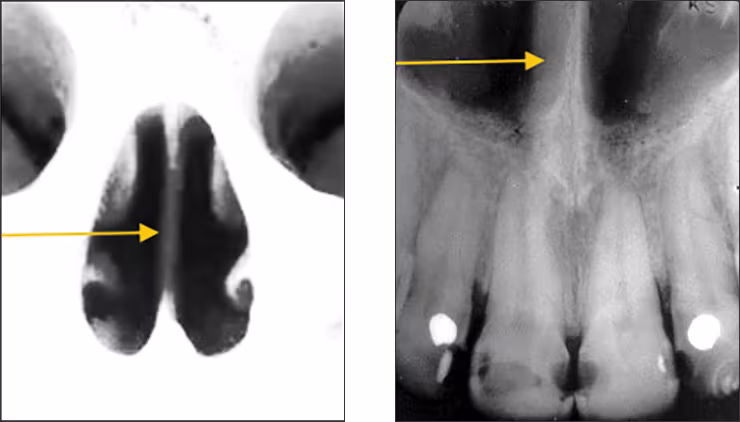

Mid-palatine suture – The mid-palatine suture is the interface of the two halves of the premaxilla where they come together in the midline. The mid-palatine suture is also referred to as the median palatal suture. It courses from the alveolar crest through the midline to the posterior aspect of the hard palate. This structure appears radiographically as a thin vertical linear radiolucency in the midline on maxillary central incisor periapical images.

Incisive foramen – The incisive or nasopalatine foramen is located in the midline on the lingual aspect of the hard palate above the central incisor teeth crowns. The foramen is the termination of the nasopalatine canal. Radiographically, it appears between the roots of the central incisor teeth as a round to oval radiolucency less than one centimeter in diameter. It has a range of sizes and shapes, so variation is not unusual. This structure is recorded on maxillary central incisor periapical images.